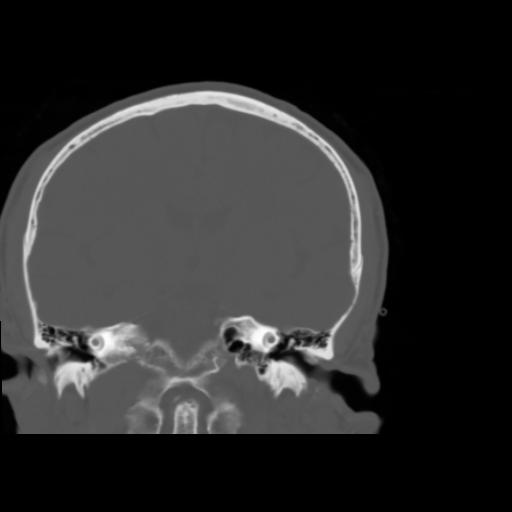

5 CEREBRO,,Coronal,3.000,CEREBRO,Coronal,